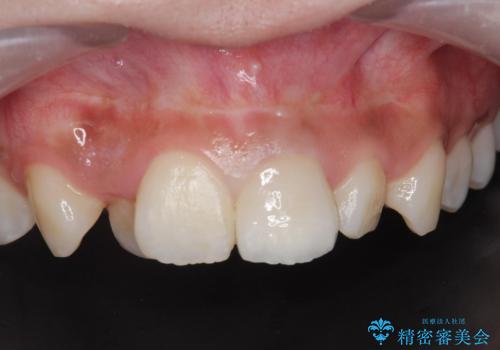

綺麗な被せ物が入り大変満足して頂けました。

根の治療のやりかえは希望されなかったので土台だけやりかえを行い、ジルコニアクラウンで治療を行いました。